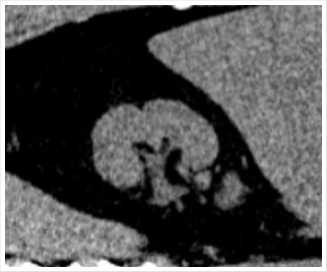

Рис. 8. МСКТ в нативном режиме, сделанная в июле 2024 г., отмечается полный литолиз конкрементов.

Учитывая проведение успешной литолитичекой терапии в анамнезе, пациентке повторно проводилась терапия цитратными смесями и вспомогательными препаратами курсом до 3 месяцев. При контрольной КТ мочевой системы, выполненной в июле 2024 г. отмечена полная элиминация конкрементов правой почки (рентгеноконтрастных конкрементов в почках, мочеточниках, мочевом пузыре не выявлено) (Рис. 8).